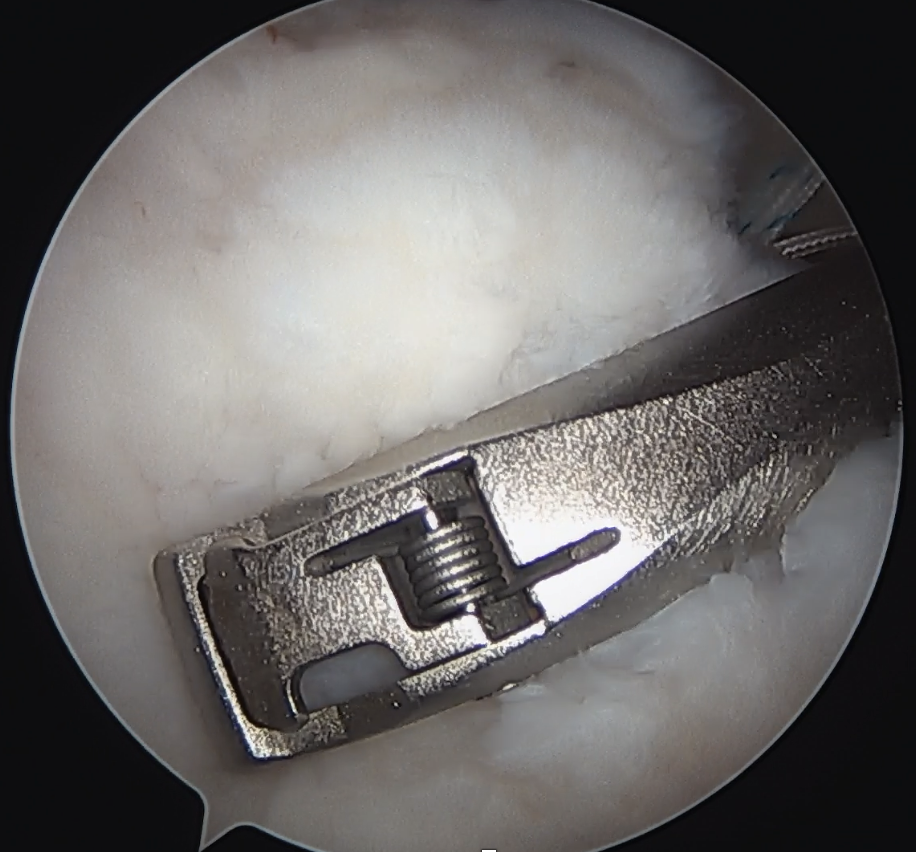

Single row anchor

- insert anchors at lateral edge of footprint

Double row anchors

- medial anchor row at articular margin and tie through medial cuff

- lateral anchor row at lateral footprint used to secure sutures

- increase surface area of cuff repaired to foot print

Trans-osseous equivalent / suture bridge

- cross sutures from medial row to lateral row

- increase contact between cuff and footprint